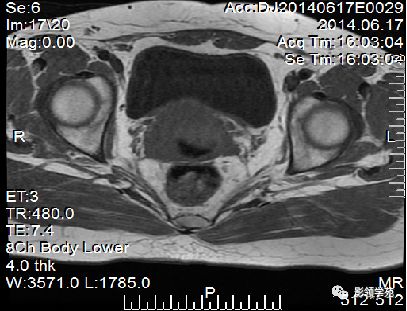

正常MR表现:卵巢和输卵管

卵巢:轴位和冠状面显示较佳,T1WI为中等或稍低信号,T2WI可因多个卵泡结构表现为高信号,但其间质部分仍呈稍低信号

输卵管:无法显示